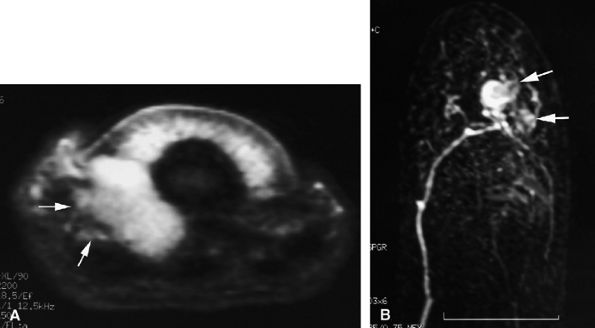

Nodular or tubular enhancement may be seen after gadolinium administration. MRA is complementary to standard MR studies, providing precise details of the angiographic appearance of the malformation (Fig. 11.78). MRA of the fingers is technically challenging because of the small caliber of blood vessels and their changing orientation. The MRA technique that is most suited to the fingers is a 3D coronal acquisition after gadolinium administration. This rapid technique (requiring less than 30 seconds for acquisition) yields high spatial resolution and is not dependent on vessel orientation. Injection of a gadolinium test dose allows precise determination of maximum arterial enhancement.180 Temporal resolution remains inferior to DSA.4

FIGURE 11.78 ● Venous malformation. (A) Axial post-contrast fat-suppressed T1-weighted image showing vascular malformation invading the fourth intermetacarpal space and the fifth metacarpal (arrows). (B) MR angiogram of multifocal vascular malformation with a distal extension toward the lateral aspect of the fifth finger (arrows).